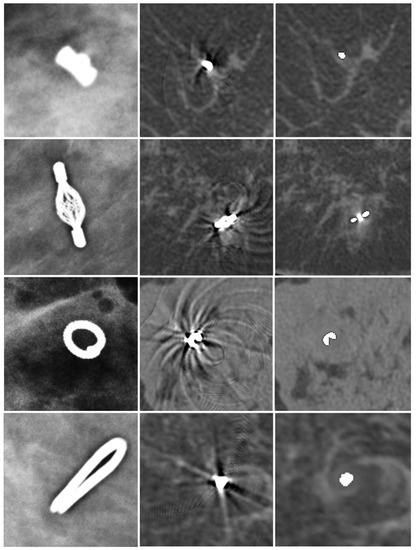

| Marker | Company | Material | Size | Number of Cases |

|---|---|---|---|---|

| O-Twist | BIP Medical | Nitinol | 18 G, Diameter 3.8 × 3.8 mm | 13 |

| Tumark Vision | Somatex | Nitinol | 18 G, Diameter 7.0 × 3.5 mm | 4 |

| SecurMark (Top hat shape) | Hologic | Titanium and bioabsorbable glycoprene netting | 9 G, Diameter 1.8 × 0.9 mm (radiopaque), 15 mm netting | 1 |

| Ligaclip (surgical clip marker) | Ethicon | Titanium | 9.0 × 1.2 × 1.0 mm | 2 |